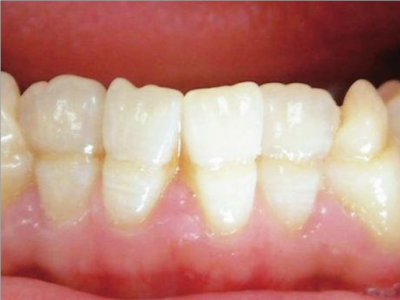

牙釉质发育不全牙齿变薄图

牙釉质发育不全患者的牙齿有色泽和透明度改变,表面出现白垩色釉质,同时牙齿顶端变透明、变薄,但患者可能无敏感、疼痛等自觉症状。